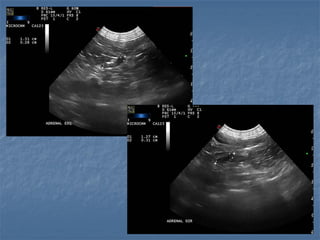

Técnica de varredura

Plano de imagem - long

 Imagem é aparelho

dependente!

 Necessário alta

resolução para

observar detalhes

 Imagem éaparelho dependente!  Necessário alta resolução para observar detalhes